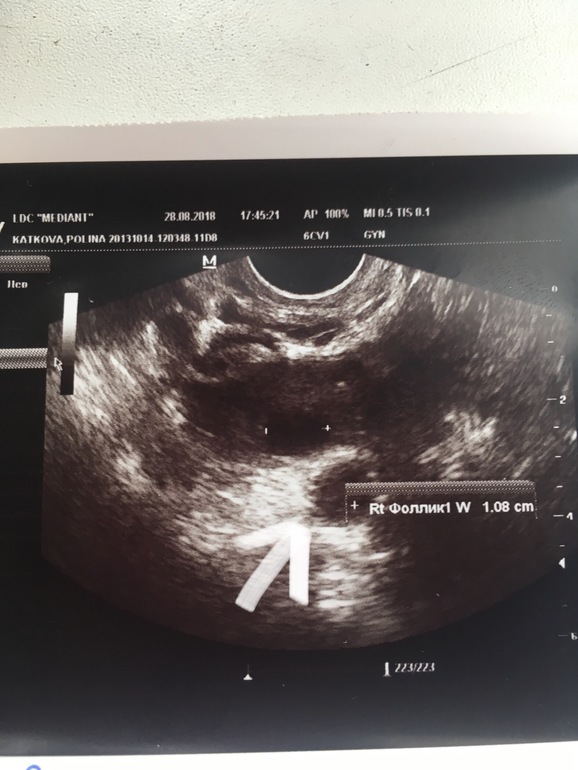

Левый яичник посмотрели нормально, а правый буквально засунули датчик и сказали тут ничего нет и все. Хорошо хоть снимок есть. Я поэтому и хотела узнать

УЗИ.. 37 ДЦ Узи